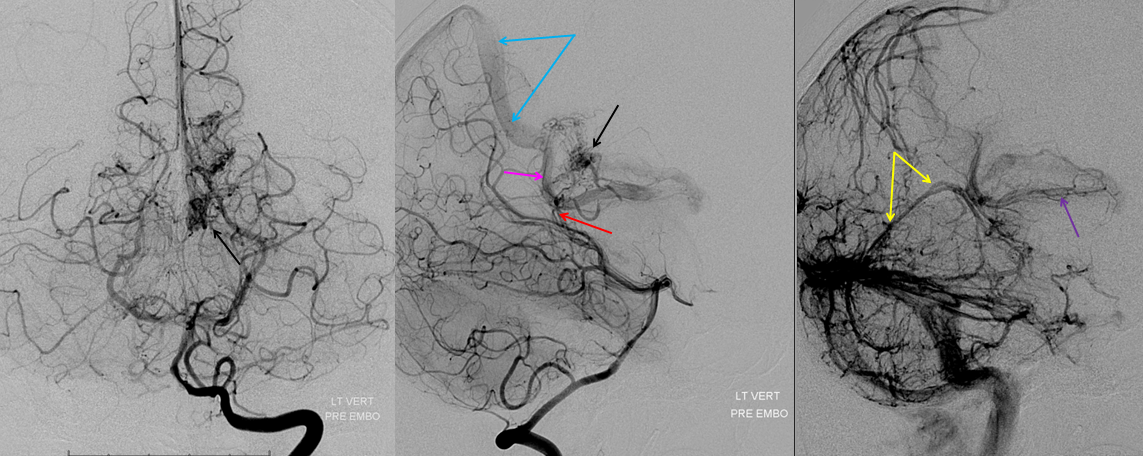

Following embolization, resection, recurrence (as frequently the case with childhood AVMs) and gamma-knife, things look good. Stereo, of course.

Following embolization, resection, recurrence (as frequently the case with childhood AVMs) and gamma-knife, things look good. Stereo, of course.